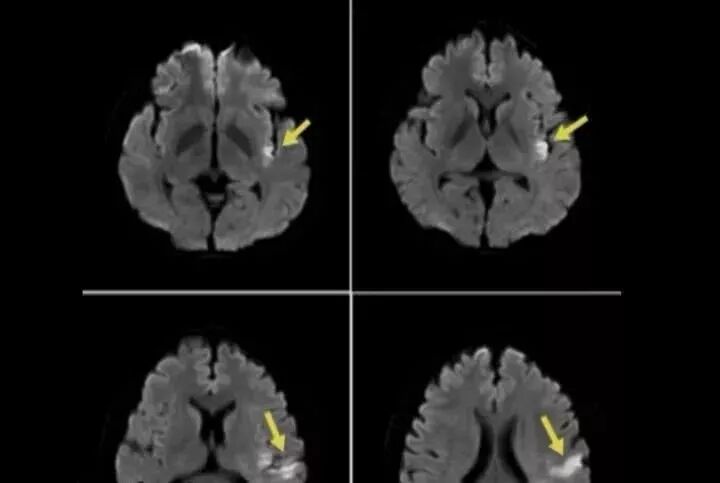

27岁的小张觉得肩颈有点不舒服,于是就去浴室按摩,但当小张离开后,感到头晕、难受,导致没法走路,当晚小张被紧急送往医院,次日抢救无效宣告身亡。原来按摩导致小张颈部错位,引发脑梗塞,致中枢神经功能障碍而死。